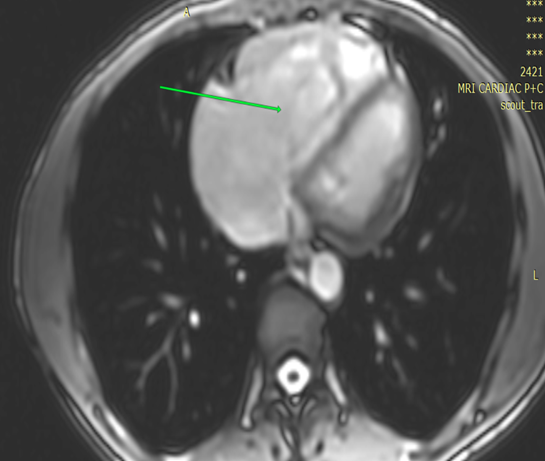

Cardiomyopathies | Jun 25, 2025

A Case of Arrhythmogenic Right Ventricular Cardiomyopathy with Symptomatic Arrhythmia

Arrhythmogenic right ventricular cardiomyopathy (ARVC) is an inherited myocardial disease; the hallmark of which is progressive fibro-fatty replacement of the...Read More